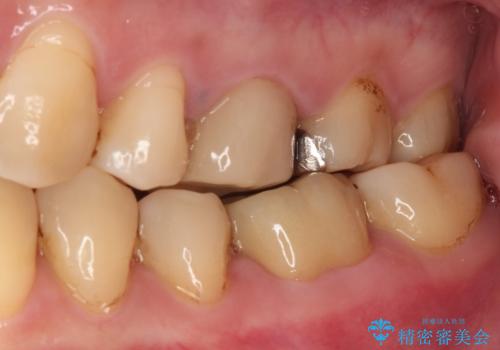

フルジルコニアクラウンは、やや光沢のある材質ですが、奥歯に装着した場合にはさほど気にならず、自然な口元の印象となりました。